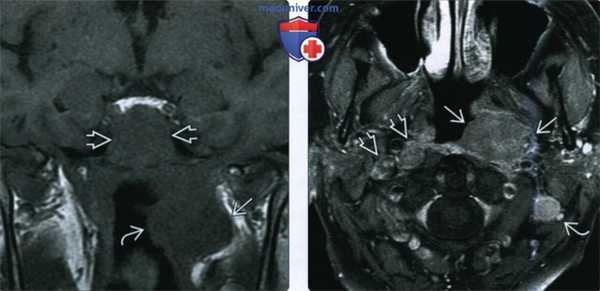

(Слева) При МРТ Т1ВИ в корональной проекции в верхних боковых отделах носоглотки В визуализируется объемное образование с гипоинтенсивным сигналом, инфильтрирующее скат и левое окологлоточное пространство. Была выполнена эндоскопическая биопсия, подтвердился некератинизирующий рак носоглотки.

(Справа) При МРТ Т1 С+ FS в аксиальной проекции у этого же пациента в левом боковом кармане носоглотки визуализируется объемное образование (рак), распространяющееся в окологлоточное пространство. Хорошо видны вторично измененные контрлатеральные заглоточные лимфоузлы и ипсилатеральные (уровень ИВ) лимфоузлы (третья стадия, T3N2).